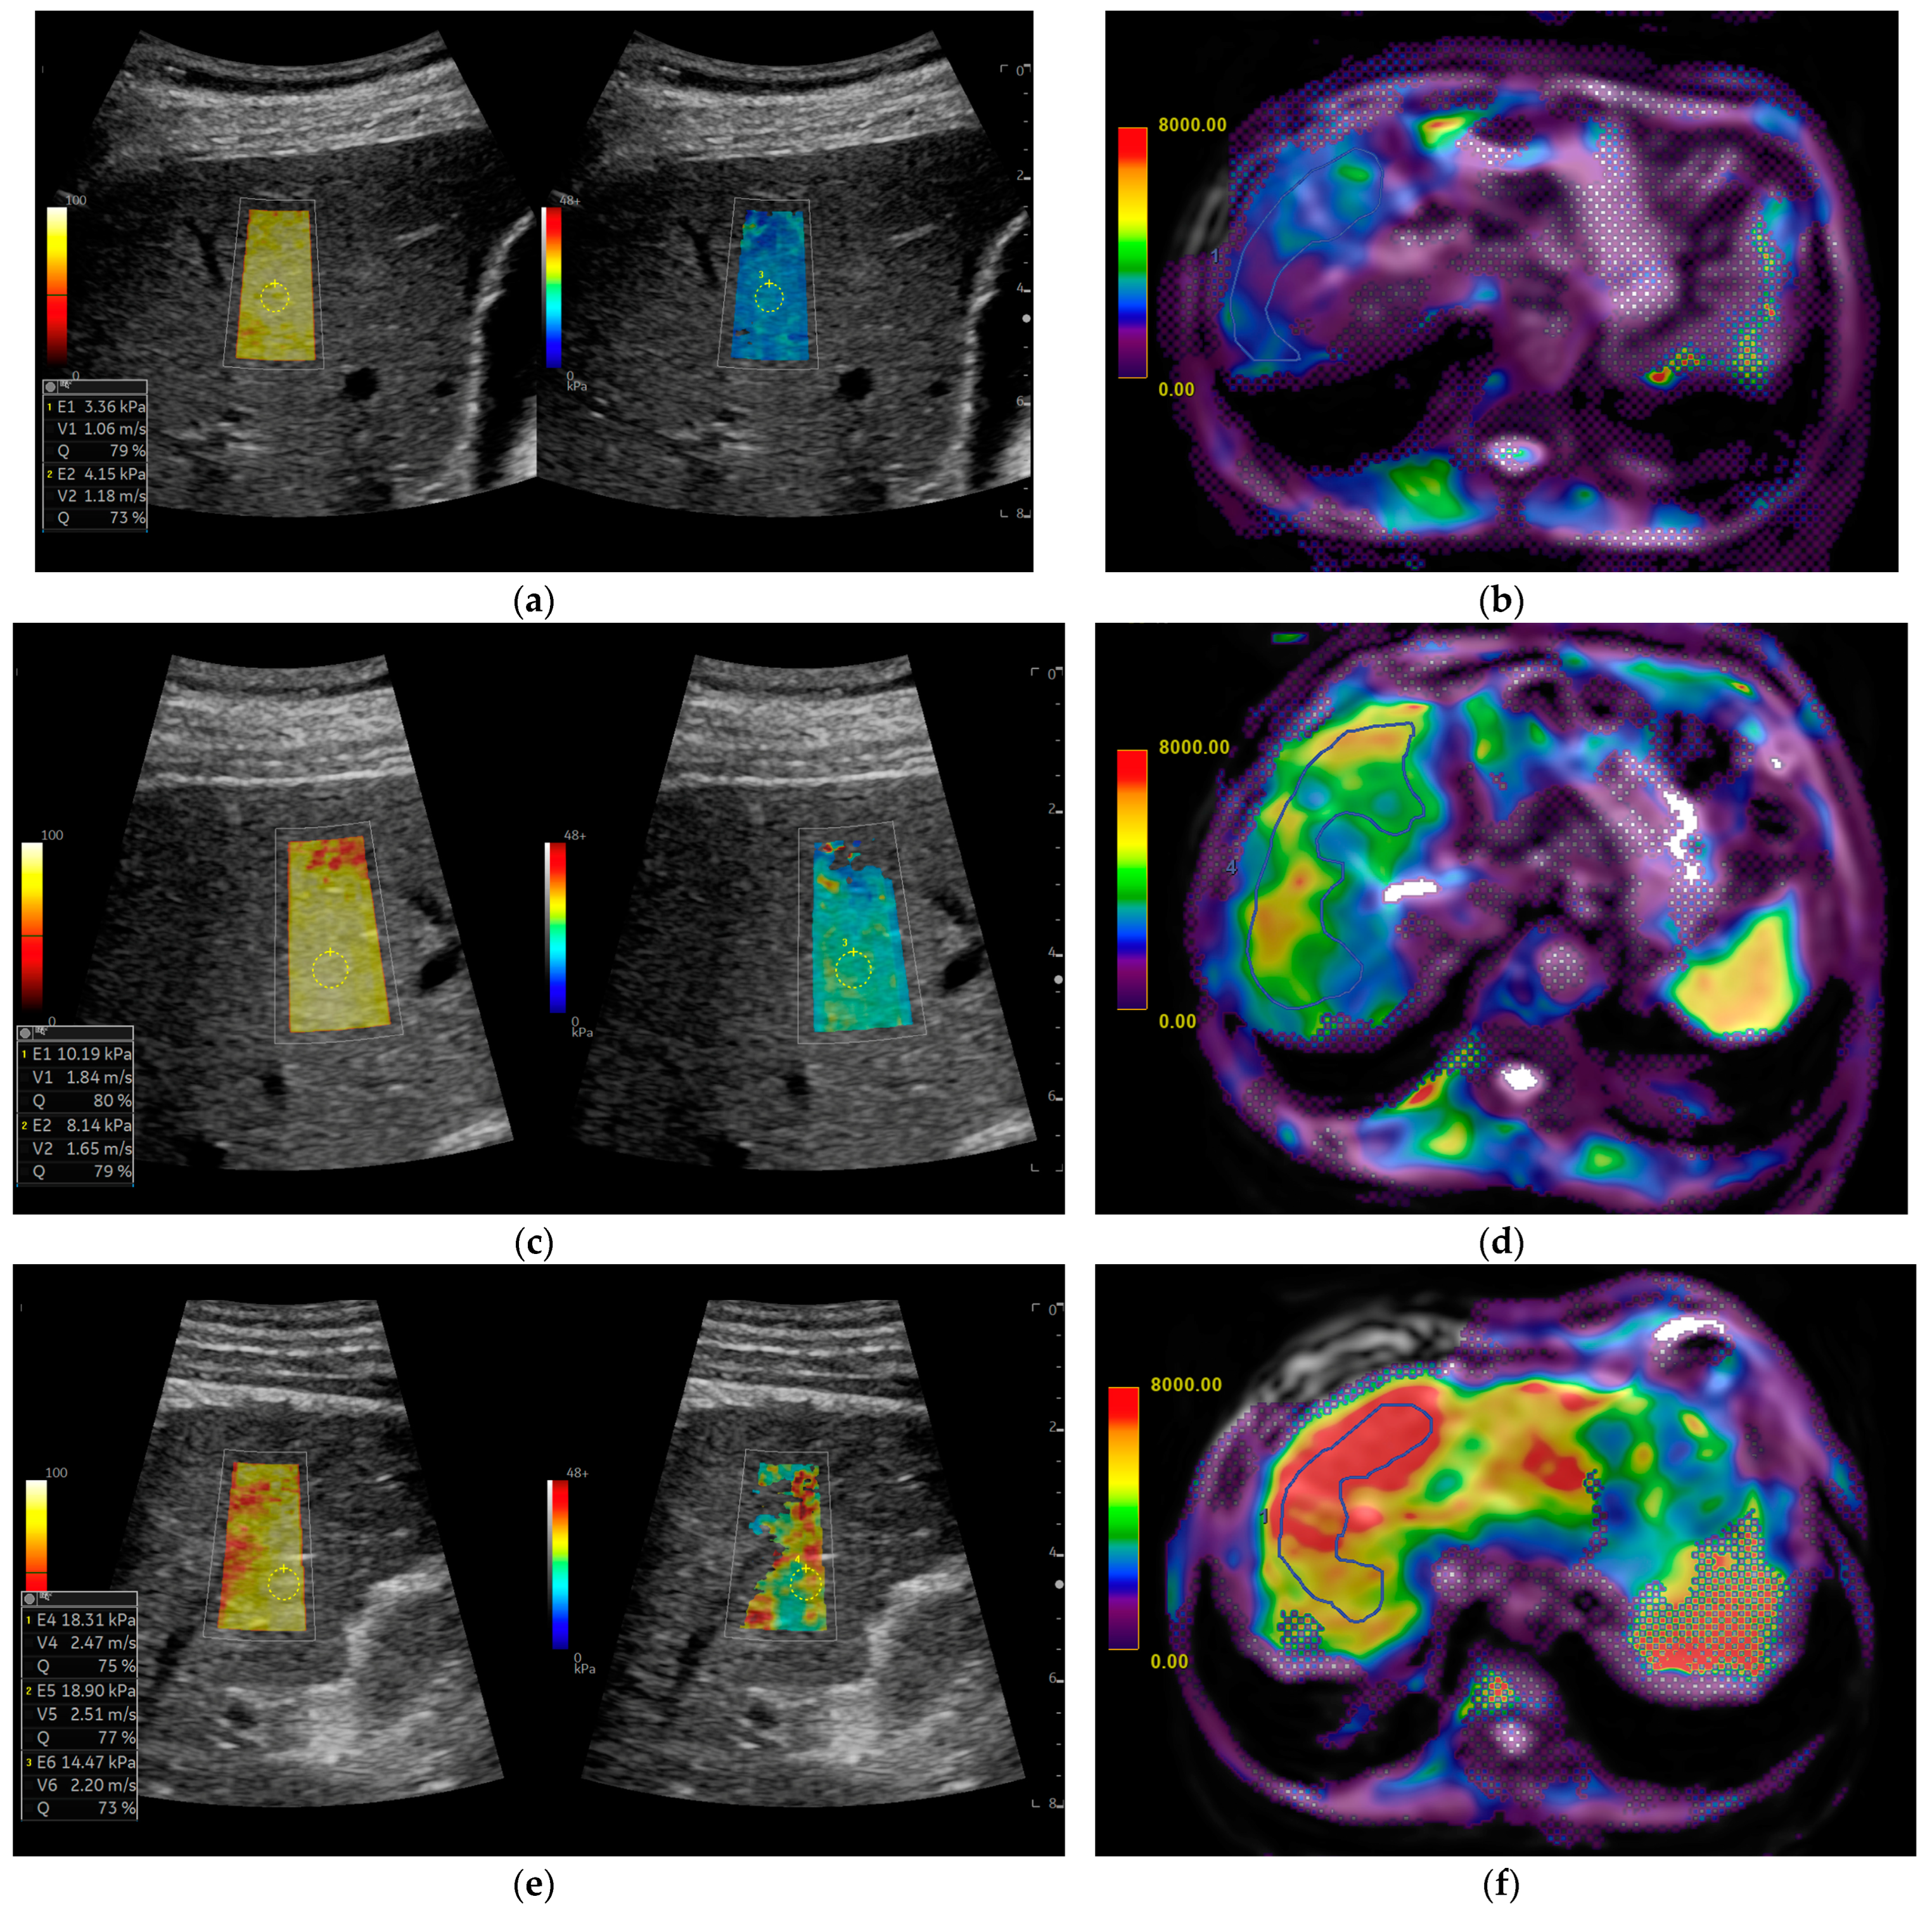

In each patient, liver stiffness measurements were obtained using both 2D-SWE and MRE, as shown in Figure 2.

Figure 2. Comparison of liver stiffness using 2D shear-wave elastography (SWE) and magnetic resonance elastography (MRE) across fibrosis stages: (a,b) normal liver stiffness, with low values in (a) 2D-SWE and (b) MRE; (c,d) intermediate fibrosis; and (e,f) cirrhosis, F4, with high stiffness in both 2D-SWE and MRE. Each pair (a-b, c-d, e-f) represents the same patient at different fibrosis stages. ROIs are also shown in the images as stiffness measurements.